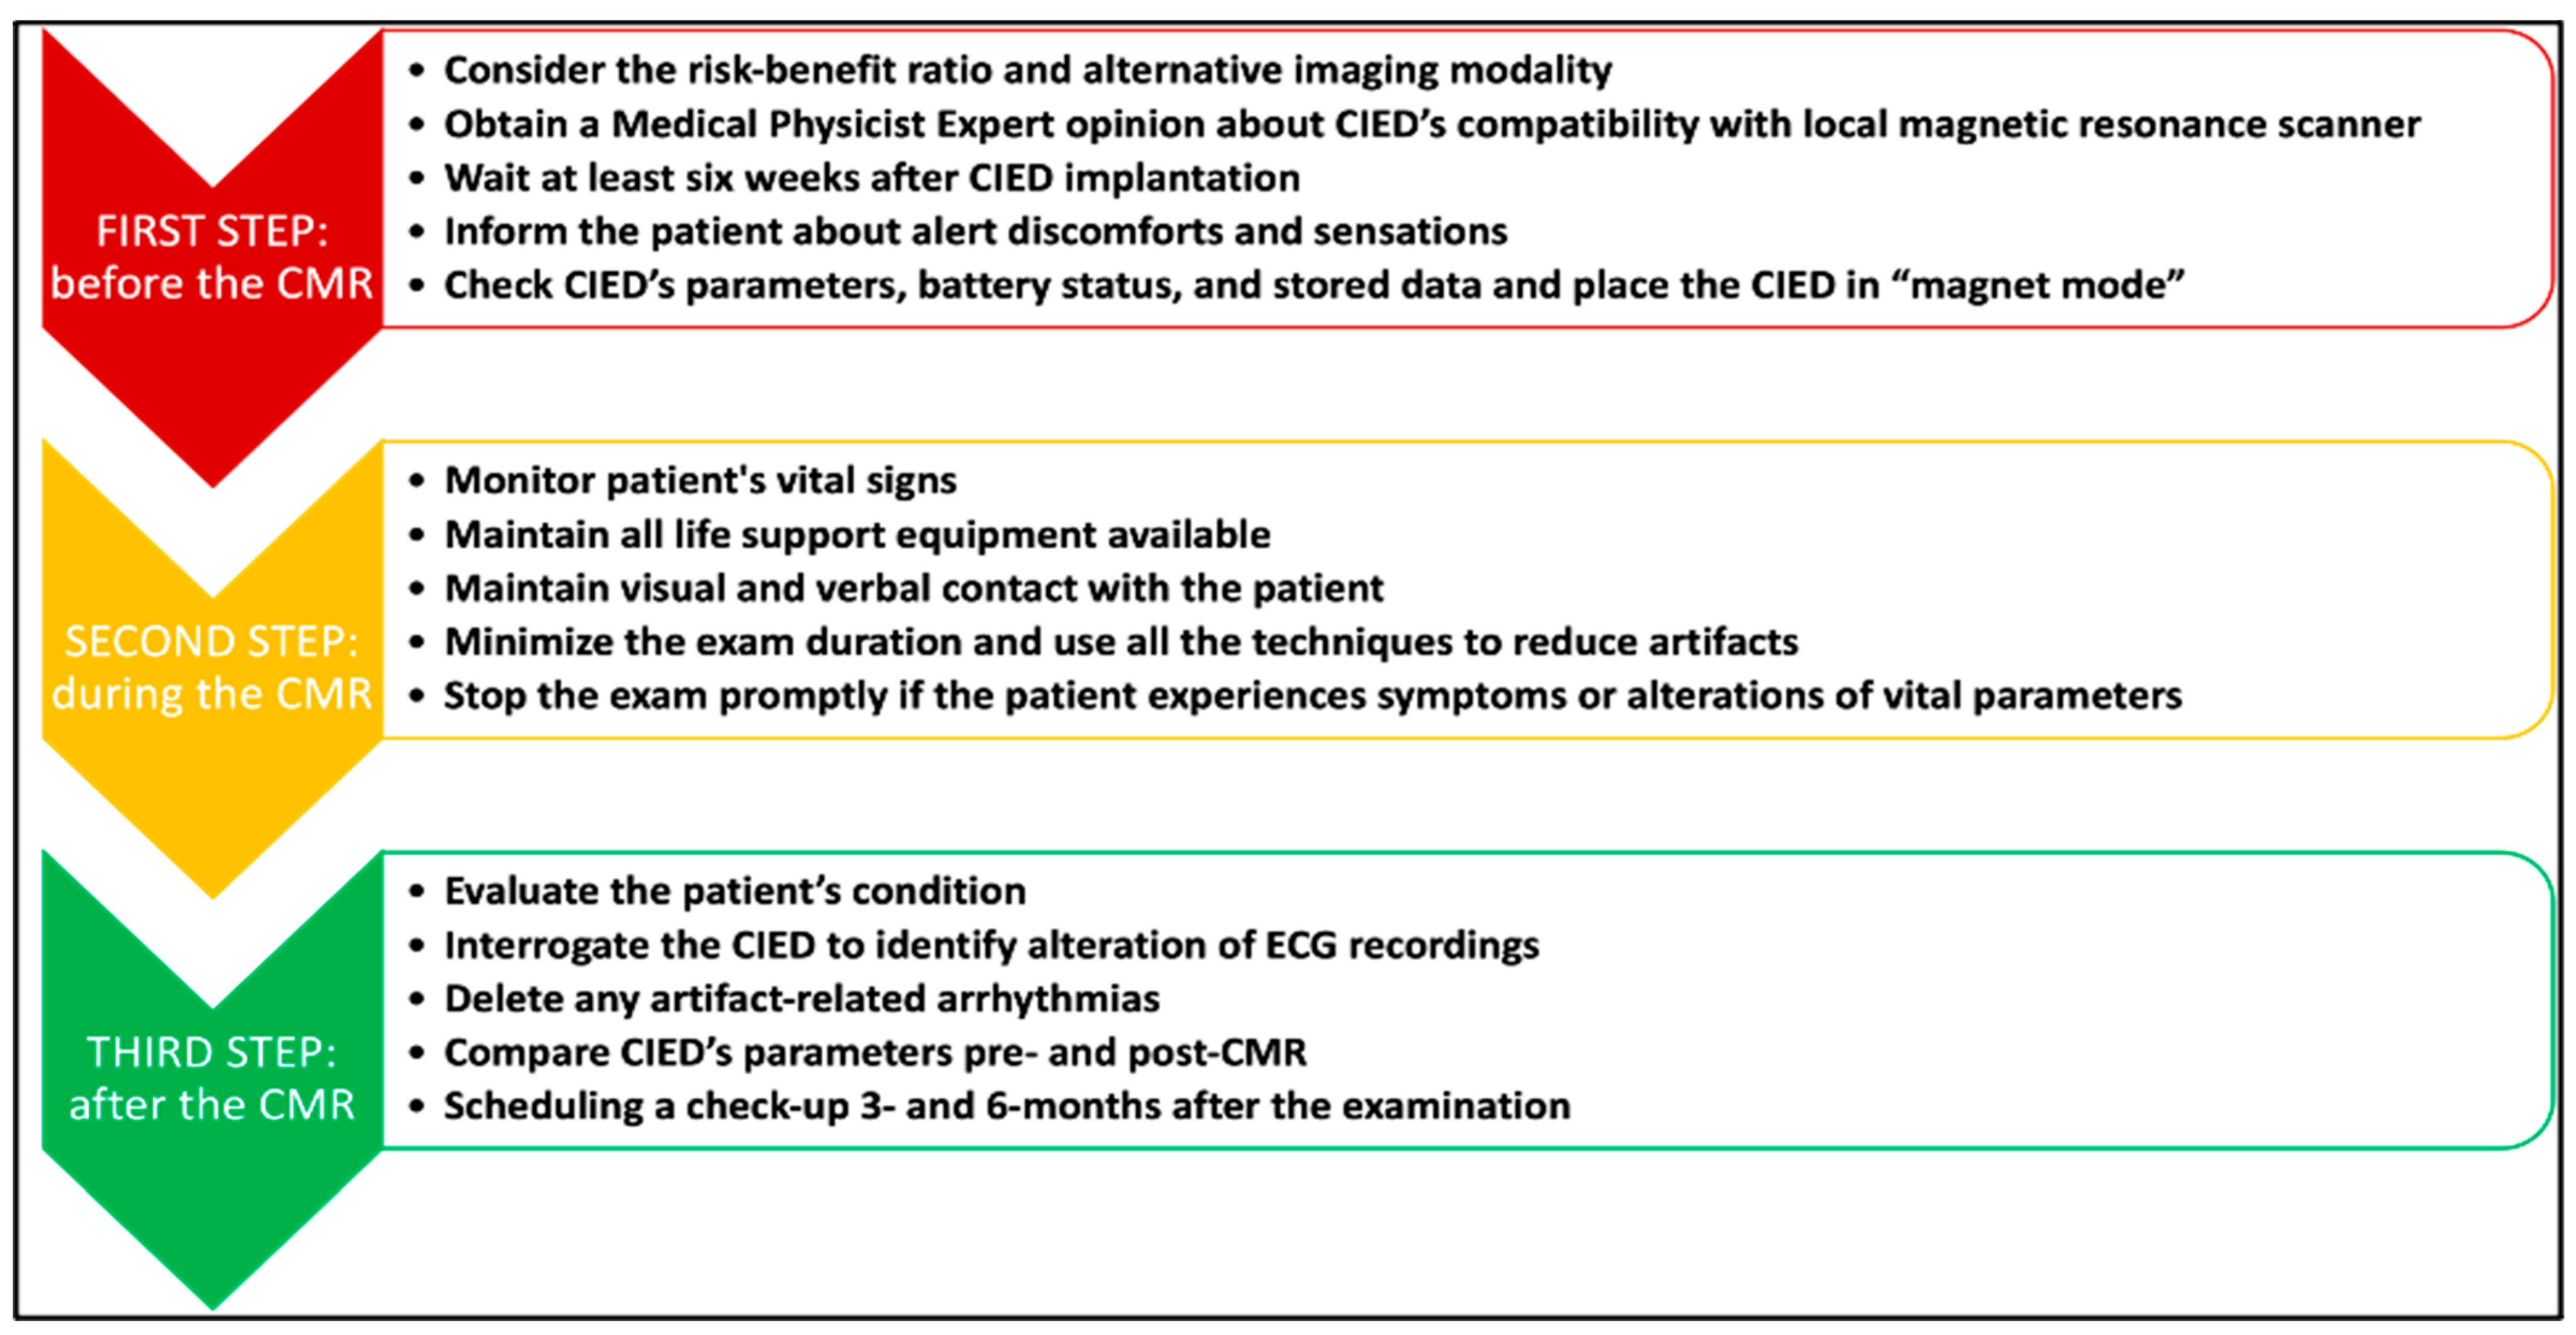

7. Clinical Protocol for Patients with CIEDs Undergoing CMR